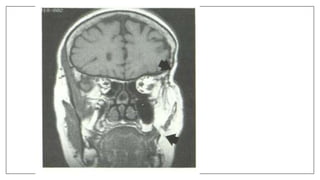

MRI in space infection

• Used in deep neck space infection: Retropharyngeal and Parapharyngeal